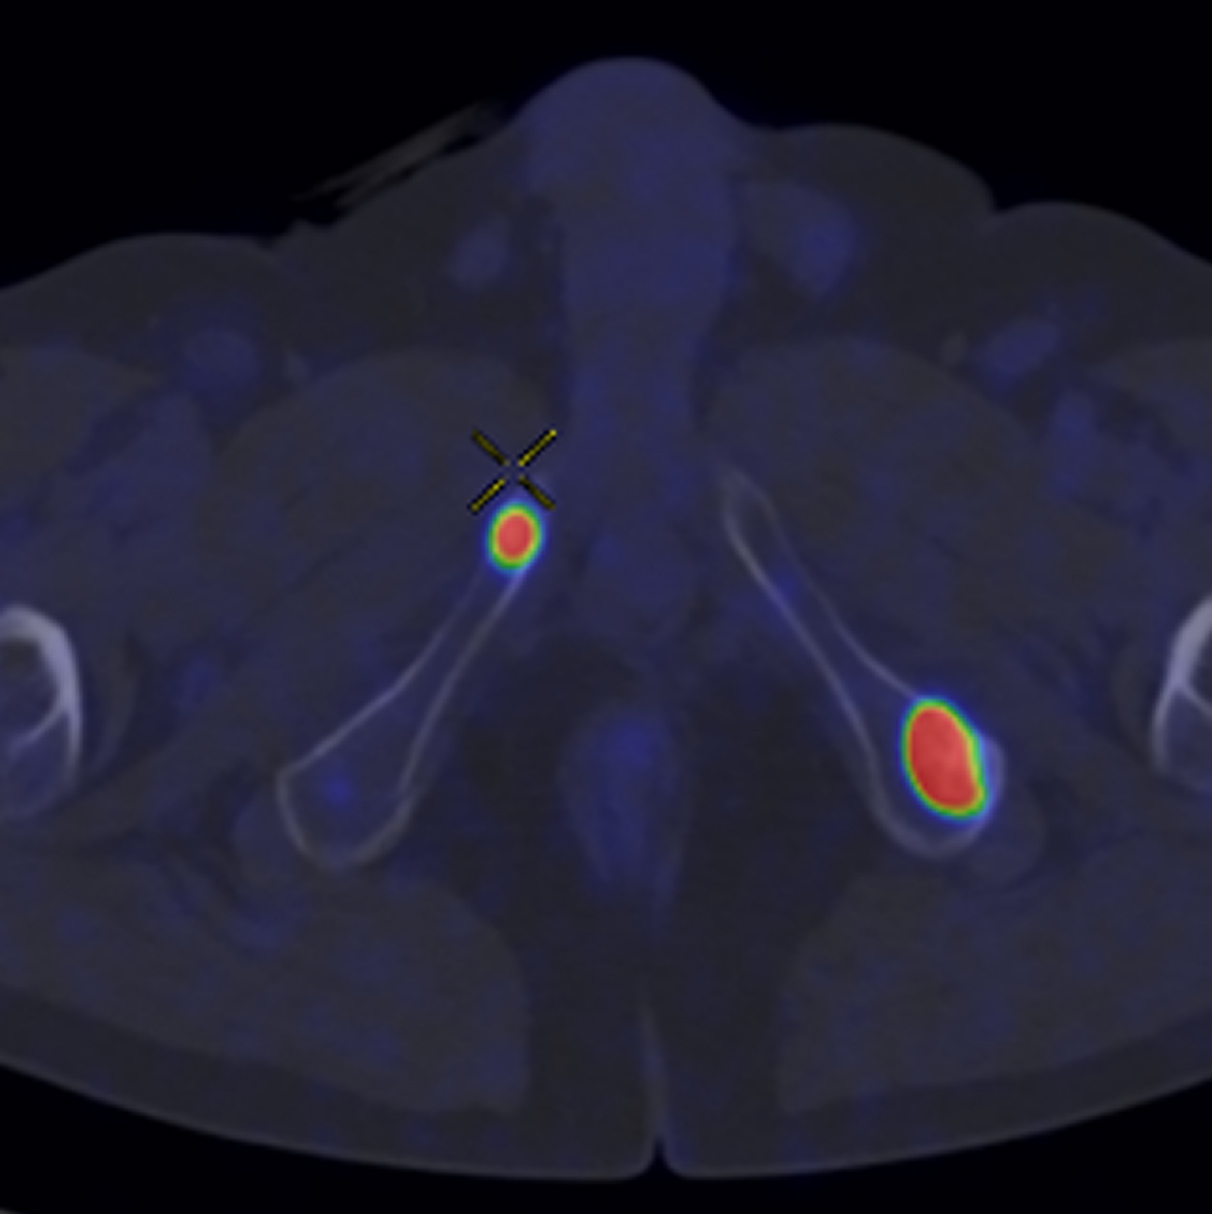

Caso condiviso da Saima Mushtaq

Paziente con anamnesi di malattia coronarica e pregresso impianto di stent sulla discendente anteriore sinistra.